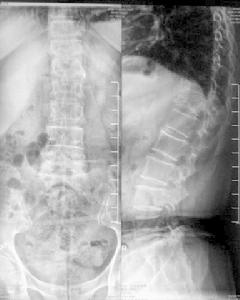

病理性骨折X片內分泌紊亂由甲狀旁腺腺瘤或增生引起的甲狀旁腺功能亢進,可導致骨的脫鈣及大量破骨細胞堆積,骨小梁為纖維組織所取代。此時雖有新骨形成,但只能形成纖細的編織骨或非鈣化的類骨組織,而極易發生多發性病理性骨折。

2.骨質疏鬆(osteoporosis)老年、各種營養不良和內分泌等因素可引起全身性骨質疏鬆,表現為骨皮質萎縮變薄,骨小梁變細、數量減少。主要影響脊椎骨、股骨頸、掌骨等。老年尤其是絕經後老年婦女胸、腰椎壓縮性骨折,股骨頸、肱骨上端及橈骨下端骨折較為多見。肢體癱瘓、長期固定或久病臥床等可引起局部廢用性骨質疏鬆而造成骨折。

3.內分泌紊亂由甲狀旁腺腺瘤或增生引起的甲狀旁腺功能亢進,可導致骨的脫鈣及大量破骨細胞堆積,骨小梁為纖維組織所取代。此時雖有新骨形成,但只能形成纖細的編織骨或非鈣化的類骨組織,而極易發生多發性病理性骨折。

4.骨的發育障礙有多種屬於這類的先天性骨疾患可以引起病理性骨折。例如先天性成骨不全(osteogenesisimperfecta),為一種常染色體顯性遺傳性疾病,在胎兒或兒童時期發病,乃由於先天性間充質發育缺陷,不易分化為骨母細胞,同時骨母細胞合成骨基質中Ⅰ型膠原纖維障礙,因此長骨骨皮質很薄,骨細而脆,極易發生多發性病理性骨折,故又稱為脆性骨綜合徵(brittlebonesyndrome)。而骨折後新形成的骨痂為軟骨性,或為纖維性,難以發生骨化。

病理性骨折時,骨的原有病變往往使骨折癒合遲緩,甚至幾乎沒有修復反應。也常使骨原有病變的組織學圖像發生改變或複雜化。